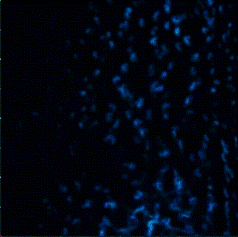

Surface(Depth) view